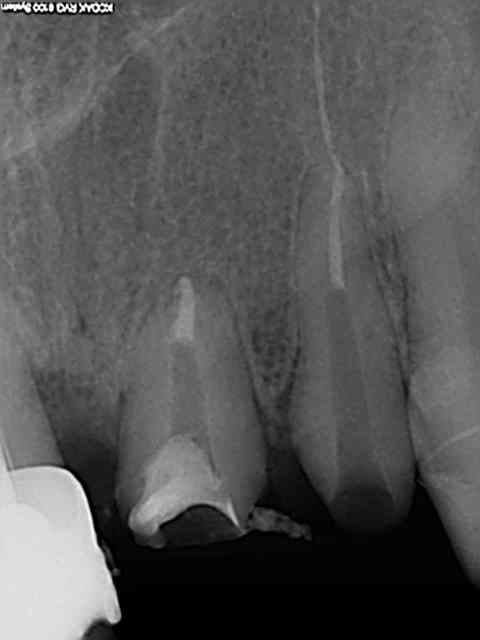

voila j ai entrepris de déposer un inlay sur 21 22 ci joint radio : j y arrive pas : j ai détouré l inlay de 22 pour lui donner ne forme arrondi , fait une tranchée entre l inlay et la dentine et j ai passé les ultrasons pneumatiques et les ultrasons classiques

ça me fait transpirer : j ai peur que ca se termine en extraction par ma faute si je fracture la dent toute grignette un conseil ?